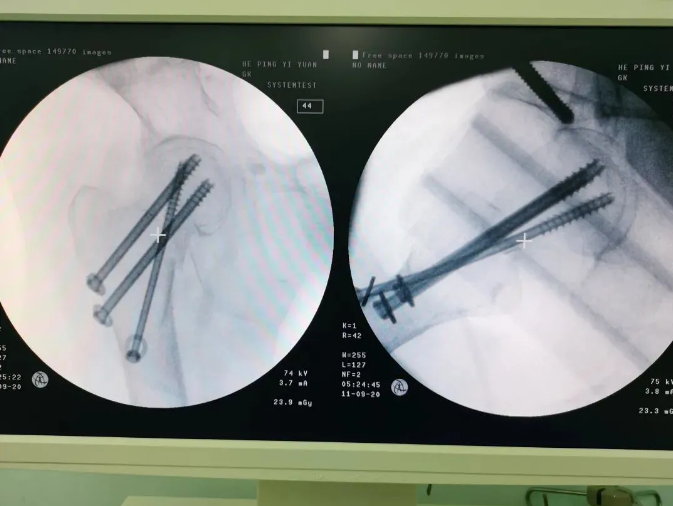

1606114906640063.png

規劃入路

1606114952897466.png

天璣機器人置入螺釘

1606115053799822.png

螺釘置入后